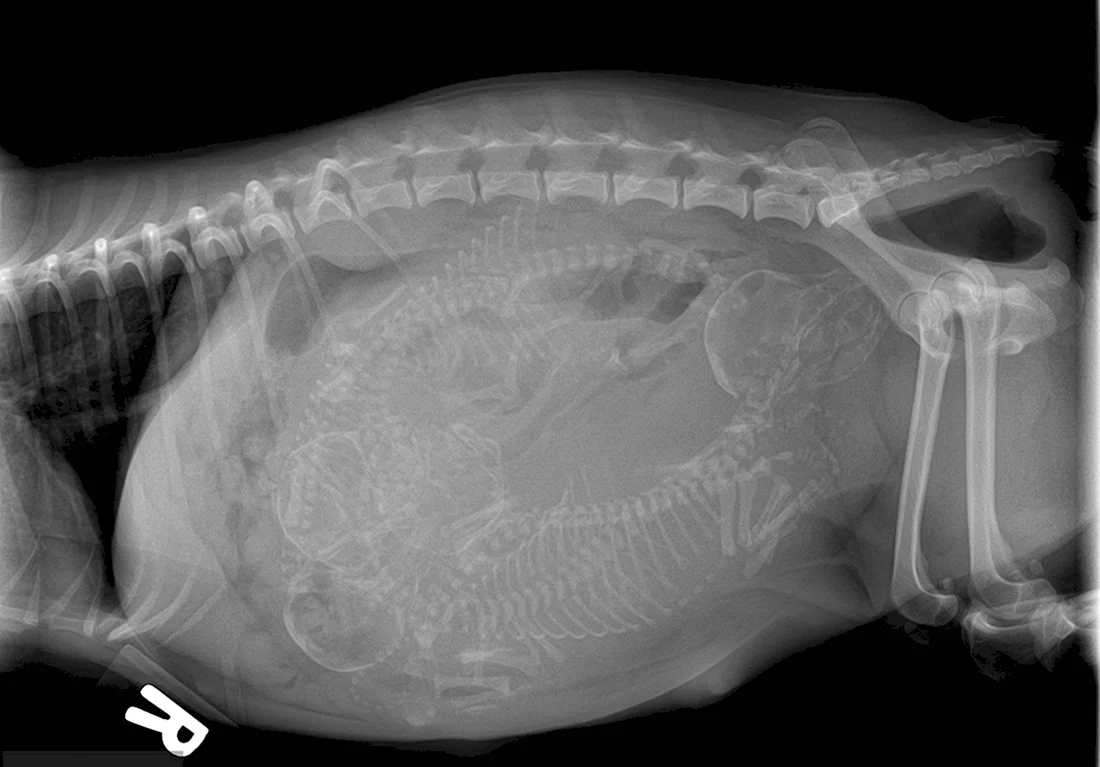

Погрузитесь в волшебный мир развития эмбриона кошки с помощью этой захватывающей галереи фотографий! Вас ждут 39 потрясающих фото и картинок, которые позволят вам увидеть каждый этап развития эмбриона. Эта подборка фотографий сразу привлечет ваше внимание и заставит задуматься о том, насколько удивительным может быть природа. Порадуйте свои глаза этой удивительной коллекцией фотографий и узнайте больше об удивительной жизни эмбрионов кошек!